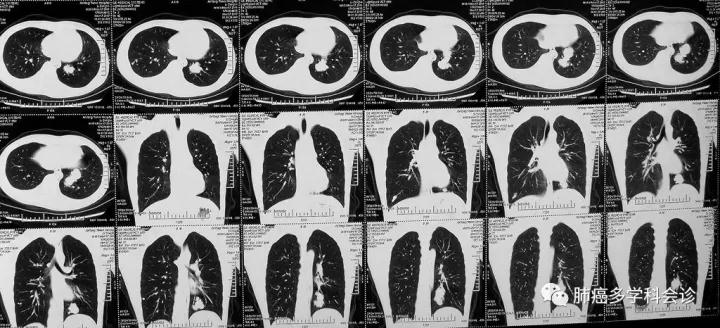

3.  此患者的肺内转移灶几乎完全钙化,也是造成延误诊断的原因之一。下图为另外一位年青骨肉瘤患者肺转移的CT图像,肺占位既有钙化又有软组织成分,不易被误诊。